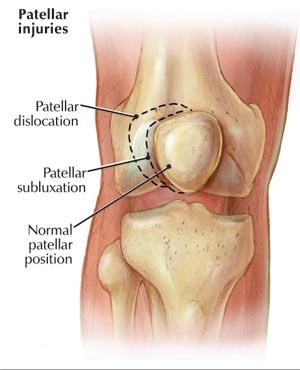

Il y a des degrés de blessures varing Patella de subluxation rotulienne jusqu'à Patella Luxation.

Patella Sublaxation est l'endroit où l'une rotule instable, ou rotule, ne détecte pas au centre de la rainure à l'extrémité de l'os de la cuisse que le pli du genou, ce qui provoque une gêne pour les côtés du genou. Cela peut être courante chez les jeunes athlètes, et peut être héréditaire.

Patella luxation est l'endroit où la rotule est délogé de la gorge, et il se produit normalement de deux façons: